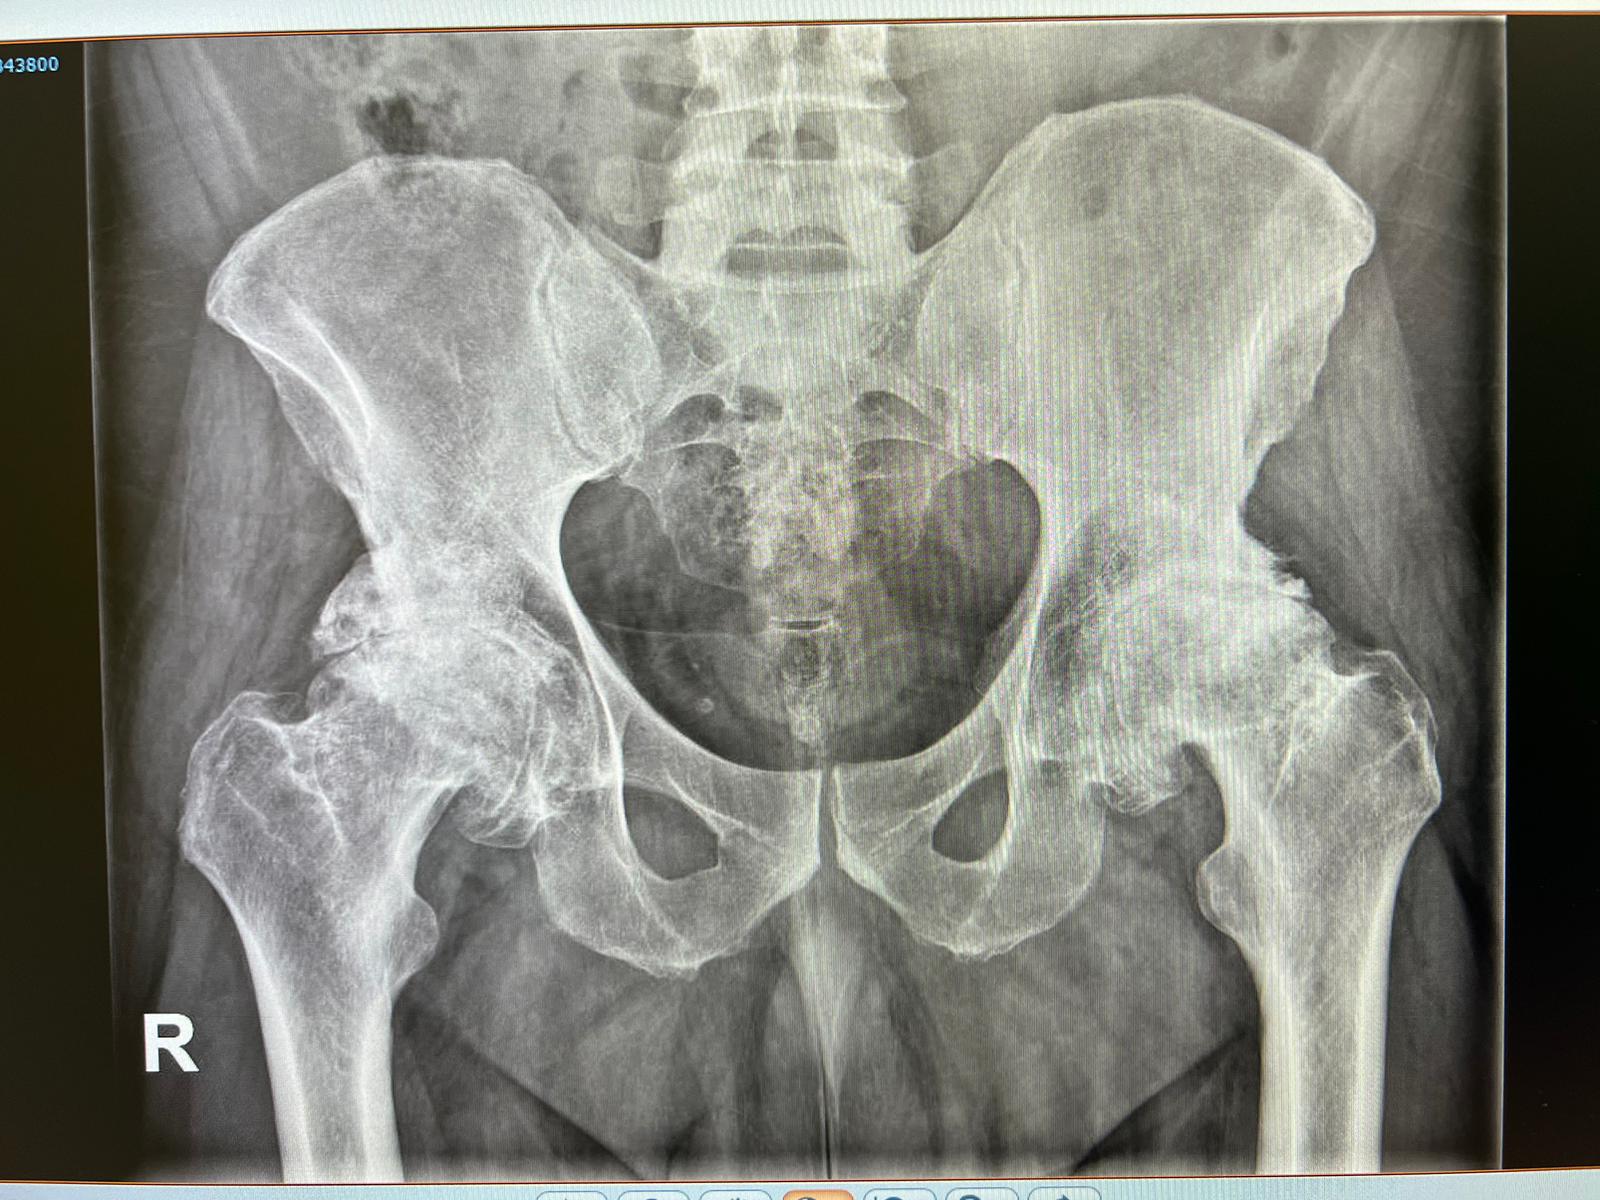

En esta colaboración, el Doctor Guadilla ha tomado parte en una compleja cirugía para incorporar en el paciente una prótesis de cadera bilateral y simultánea a través de un abordaje anterior directo. Lo sustancial en esta ocasión es que al paciente se le ha operado a la vez de las dos prótesis de cadera al presentar una artrosis muy simétrica y limitante.